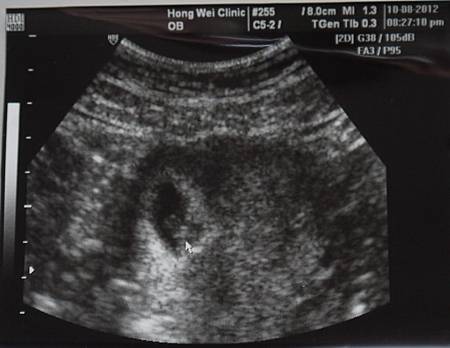

【7W】心一跳,開始煎熬XD

2012‧10‧08

照約定一個禮拜後要看看心跳

真的很好奇

這傢伙在我肚子偷長一顆心臟是啥樣

醫生很開心的說

妳看,這個小亮點就是他的心跳

當下看到一坨黑黑的當中有一閃一閃

閃爍的速度之飛快

我的腹仔裡真的有個小小人兒

看到他這麼努力的在跳阿跳的